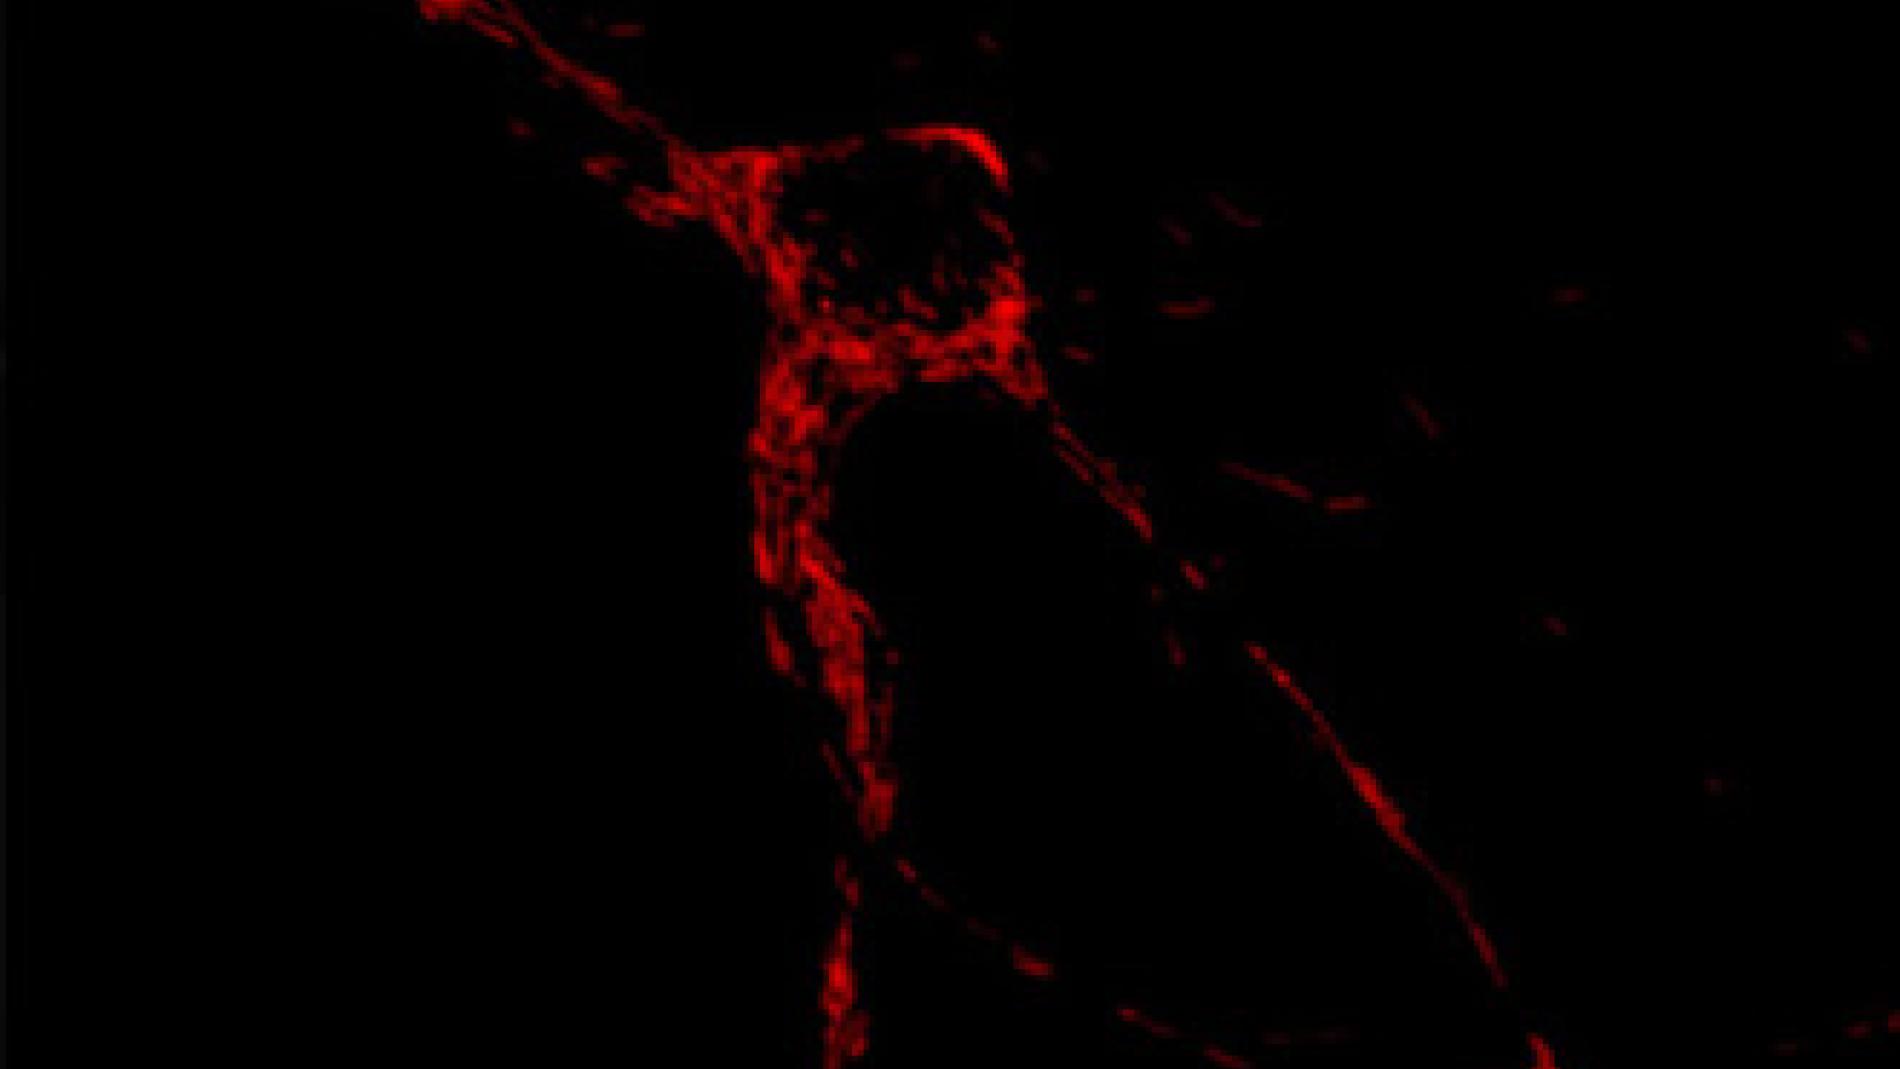

Un equip de l’Institut de Recerca Biomèdica liderat per Eduardo Soriano descriu a la revista Nature Communications una nova família de sis gens que regulen el moviment i posició de les mitocòndries a les neurones. Moltes malalties neurològiques que inclouen el Parkinson o diverses variants de la malaltia de Charcot-Marie-Tooth es deuen a alteracions de gens que regulen el transport d’aquests orgànuls, que proporcionen l’energia necessària per al funcionament de les cèl·lules.Els investigadors del grup de patologia neuromuscular i mitocondrial del Vall d'Hebron Institut de Recerca (VHIR), Dr. Antoni Andreu i la Dra. Elena García Arumí, han col·laborat amb aquest treball en l'estudi del paper d'aquestes proteïnes sobre la funció mitocondrial tant a nivell bioenergètic com en el manteniment de l'ADN mitocondrial. Aquest conjunt de nous gens s'expressa altament en el sistema nerviós amb una funció específica i crucial per a la seva activitat i viabilitat. A més de la seva possible participació en les patologies cerebrals, aquestes proteïnes podrien relacionar-se amb malalties metabòliques i el càncer.